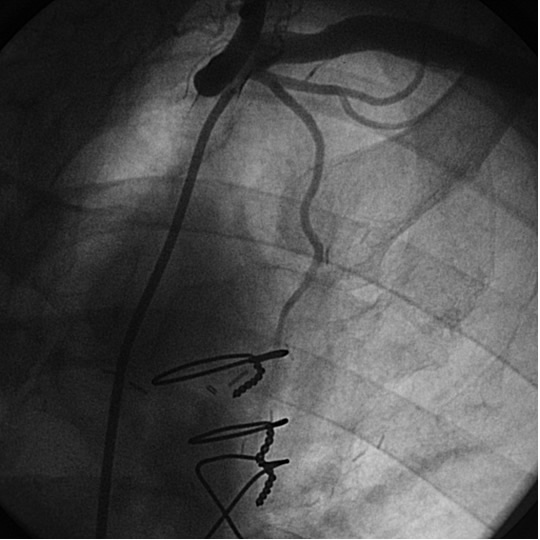

The most commonly used catheters for left heart catheterization and vein graft angiography can be seen in Figure 1 and Figure 4-13. Most of the vein grafts have horizontal take off and can be successfully engaged using a commonly used Judkins right number 4 (JR4) catheter. The JR4 catheter is the most commonly used catheter for the engagement of the right coronary ostium with horizontal take off. However, many vein grafts have unusual take off requiring different catheters. Many right coronary vein grafts have steep inferior take off making the ostial engagement with JR4 difficult or impossible (Figure 10). In such a scenario, a multipurpose catheter which has a shallow angulation is the best choice (Figure 11). The second major challenge in engaging vein graft ostia, particularly vein grafts supplying the left coronary arteries, is the shape of the aorta. A large aorta can make it very difficult for the JR4 catheter to reach the ostial vein grafts. In such a situation, Amplatz (AR) right and left (AL) catheters can be very helpful to reach the vein graft ostia. Amplatz catheters have a larger primary curve and have been used successfully in unusual superior take off of left coronary arteries or vein grafts and in large aorta. Amplatz catheters are available in different sizes (from smaller to larger curve: AR 1, AR2, AL2, AL2 and AL3). Occasionally, a very superior take off of a vein graft requires specially designed bypass graft catheters. Amplatz catheters are also extremely helpful in engaging native right coronary ostium with anterior take off.

PCI of the vein and arterial grafts have unique challenges. For any PCI, guide support is very important for successful balloon and stent delivery. In a tortuous vein graft with a steep angle, advancement of a stent can be very difficult and challenging. Therefore, it is important to choose the best available catheter before starting PCI. Similar to the right coronary angiography, a JR4 guide catheter is most commonly used in this setting. However, Amplatz guide catheters for left vein grafts and multipurpose catheters for right vein grafts are better choices in certain anatomy. In Figure 8 and Figure 10 two examples of poor guide support in two vein graft interventions can be seen. Initially, a JR4 guide was used for PCI of the vein graft supplying the left anterior descending artery (LAD) without any success. However, after changing the guide to an Amplatz left 2 guide catheter, we achieved excellent support without any difficulty in advancing two stents (Figure 9). In Figure 10, difficulty is illustrated in engaging the vein graft ostium supplying the right coronary artery with a JR4 catheter. This vein graft has a very steep inferior take off from the aorta. After changing the guide to a multipurpose catheter, we were able to deliver three stents successfully without any difficulties (Figure 11). Similar challenges exist in the treatment of the left IMA or right IMA. These arterial grafts can be extremely tortuous making stent delivery very difficult. It may be necessary to use short length stents for a better deliverability or stents with lowest profile. Usually, similar to the native coronary intervention, a 6 French guide is appropriate for the routine use.